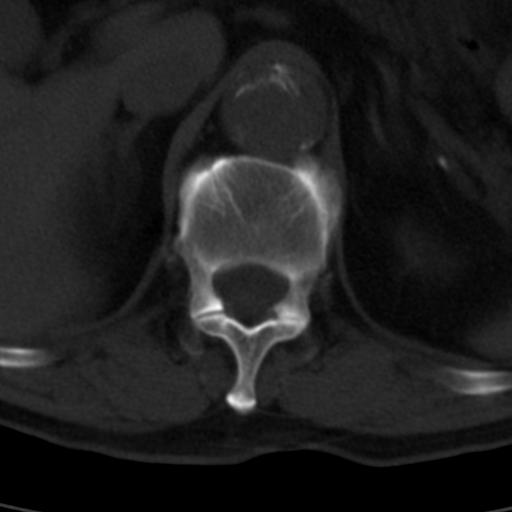

男性 82 主动脉夹层 请大家看看椎体是什么改变啊

腰椎退行性变,明显的骨赘形成,所指低密度灶为正常松质骨。